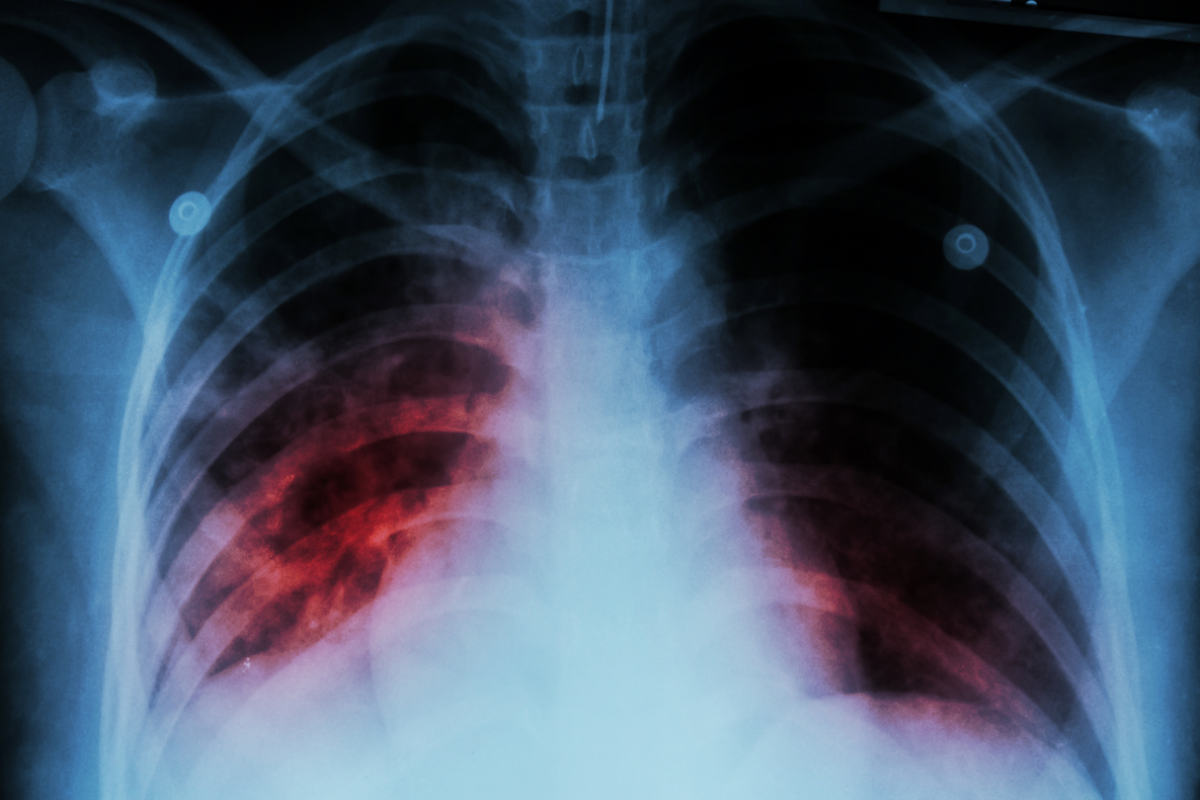

Ötən ilin yanvar-noyabr aylarında 2022-ci ilin müvafiq dövrü ilə müqayisədə ölkədə qarayara, ağciyər vərəmi ilə xəstələnmə halları azalıb. SİA xəbər verir ki, bu barədə Dövlət Statistika Komitəsinin məlumatında qeyd edilib.

Səhiyyə Nazirliyin məlumatlarına əsasən, 2023-cü ilin yanvar-noyabr aylarında 2022-ci ilin müvafiq dövrü ilə müqayisədə ölkədə qarayara ilə (39,1 faiz), ağciyər vərəmi ilə (4,2 faiz), törədicisi müəyyən olmayan kəskin bağırsaq infeksiyaları ilə (0,8 faiz), sifilis ilə (0,4 faiz) xəstələnmə halları azalıb.